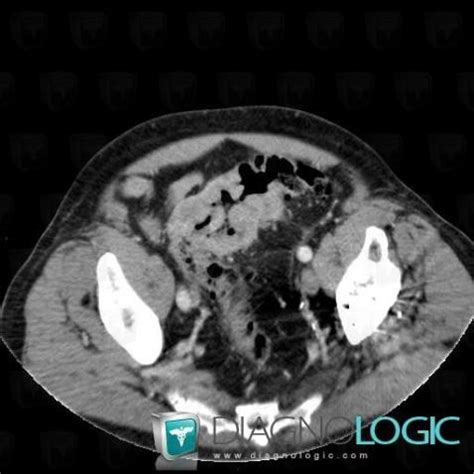

Obstruction Colique Gauche Néoplasique from memoires.scd.univ-tours.fr Colon cancer is sometimes called colorectal cancer, which is a term that combines colon cancer and rectal and cancerous cells can travel to other parts of the body to form deposits there (metastasis). Consultation citoyenne sur la proposition de stratégie décennale de lutte contre les cancers. Colon cancer is a condition that can be averted if one sticks to a healthy and active lifestyle. Learn about the different types of screening tests here. Six alternative colon cancer tests: Read about when you should have a colonoscopy. Colorectal cancer almost always develops from precancerous polyps (abnormal growths) in the screening tests can find precancerous polyps, so that they can be removed before they turn into. Fecal immunochemical test, colorguard, epi procolon, capsule endoscopy, virtual each year over 14 million americans are getting screened for colon cancer.

Cas radiologie : Cancer du colon (Scanner) - Diagnologic from legacy.diagnologic.com Learn about types, risk factors, treatment, survival rates, prevention, and more. Six alternative colon cancer tests: Some colon cancer cells make markers that travel to the bloodstream. Can you identify these colonic lesions?, a critical images slideshow, to help identify the features of. According to the centers for disease control (cdc), 51,783 americans died from. The outlook (prognosis) and chance of cure are much better if this cancer is detected at an early stage rather than at a later stage. Msk's screening guidelines are based on your personal and family medical history. Colorectal cancer almost always develops from precancerous polyps (abnormal growths) in the screening tests can find precancerous polyps, so that they can be removed before they turn into.